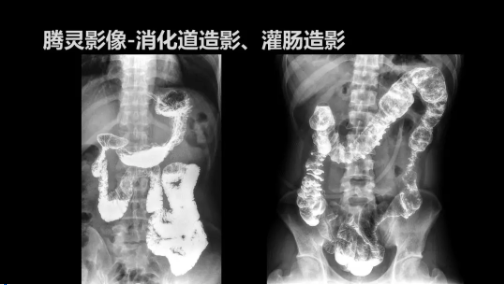

“騰靈”是安健科技的第四代動(dòng)態(tài)DR產(chǎn)品,可實(shí)現(xiàn)全科室應(yīng)用。如各類(lèi)常規(guī)的X線(xiàn)檢查、消化道檢查、骨科檢查、婦科、兒科檢查等。此外,安健科技為“騰靈”在真正意義上實(shí)現(xiàn)多科室、多功能診斷進(jìn)行了多項(xiàng)針對(duì)性設(shè)計(jì)。

此外,“騰靈”為了能夠幫助醫(yī)生更快速、有效的定位病灶,還增加了多項(xiàng)精準(zhǔn)診斷保障功能,如支持動(dòng)態(tài)觀察診斷,實(shí)時(shí)高清點(diǎn)片等?!膀v靈”透視切換高清點(diǎn)片曝光,捕捉關(guān)鍵病灶診斷僅需0.8s,同時(shí)還支持圖像局部放大,醫(yī)生可自由切換15’12’和9’三種放大模式,另外,“騰靈”還支持視頻保存、回放功能,幫助醫(yī)生在檢查結(jié)束后通過(guò)回放查看細(xì)節(jié),為醫(yī)生的診斷增加信心。